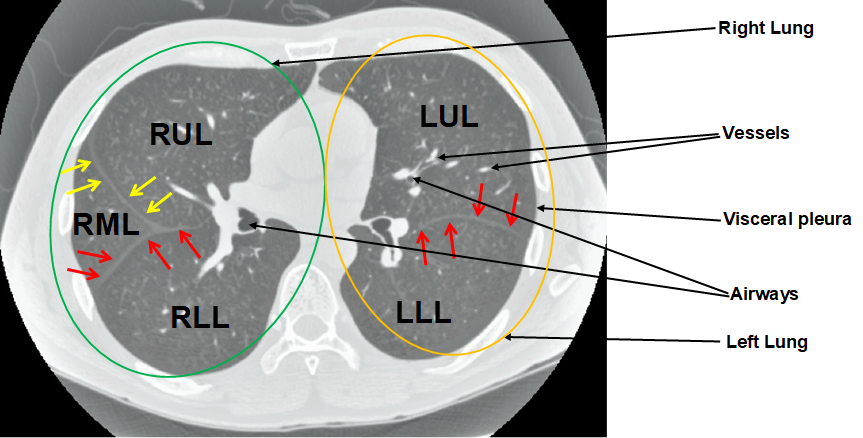

Appendix 7 presents a novel deep learning-based methodology for 3D human lung lobe segmentation.

Los Angeles, CA. \publicationHatamizadeh, A., Sengupta, D., Xu, D., and Terzopoulos, D. (2020). Few-Shot Semantic Segmentation Using Aligned Variational Autoencoders. Under review by Advances in Neural Information Processing Systems (NeurIPS). \publicationHatamizadeh, A., Sengupta, D., and Terzopoulos, D. (2020). Deep End-to-End Trainable Active Contours for Building Footprint Delineation. Under review by the European Conference on Computer Vision (ECCV). \publicationHatamizadeh, A., Hoogi, A., Sengupta, D., Lu, W., Wilcox, B., Rubin, D., and Terzopoulos, D. (2019a). Deep Active Lesion Segmentation. In the International Workshop on Machine Learning in Medical Imaging (MLMI), pages 98–-105. Springer. \publicationHatamizadeh, A., Terzopoulos, D., and Myronenko, A. (2019). End-to-End Boundary Aware Networks for Medical Image Segmentation. In the International Workshop on Machine Learning in Medical Imaging (MLMI), pages 187–194. Springer. \publicationMyronenko, A., and Hatamizadeh, A. (2019). Robust Semantic Segmentation of Brain Tumor Regions From 3D MRIs. In the MICCAI International Brain Lesion Workshop, pages 82–89. Springer. \publicationMyronenko, A., and Hatamizadeh, A. (2019). 3D Kidneys and Kidney Tumor Semantic Segmentation using Boundary-Aware Networks. In the 2019 Kidney Tumor Segmentation Challenge: KiTS19. University of Minnesota Digital Conservancy. \publicationImran, A.-A.-Z., Hatamizadeh, A., Ananth, S. P., Ding, X., Tajbakhsh, N., and Terzopoulos, D. (2019). Fast and Automatic Segmentation of Pulmonary Lobes From Chest CT using a Progressive Dense B-Network. Computer Methods in Biomechanics and Biomedical Engineering: Imaging and Visualization, November, pages 1–10. \publicationHatamizadeh, A., Hosseini, H., Liu, Z., Schwartz, S. D., and Terzopoulos, D. (2019). Deep Dilated Convolutional Nets for the Automatic Segmentation of Retinal Vessels. In Proceedings of the 15th International Conference on Machine Learning and Data Mining (MLDM’19), pages 39–48. \publicationImran, A.-A.-Z., Hatamizadeh, A., Ananth, S. P., Ding, X., Terzopoulos, D., and Tajbakhsh, N. (2018). Automatic Segmentation of Pulmonary Lobes Using a Progressive Dense V-Network. In In Deep Learning in Medical Image Analysis (DLMIA), volume 11045 of Lecture Notes in Computer Science, pages 282–290. Springer.